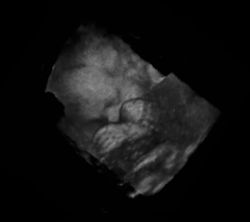

Ein wesentlicher Vorteil der Sonografie gegenüber dem in der Medizin ebenfalls häufig verwendeten Röntgen liegt in der Unschädlichkeit der eingesetzten Schallwellen. Auch sensible Gewebe wie bei Ungeborenen werden nicht beschädigt, die Untersuchung verläuft schmerzfrei.

Neben der Herztonwehenschreibung (Kardiotokografie) ist sie ein Standardverfahren in der Schwangerschaftsvorsorge. Eine spezielle Untersuchung der Pränataldiagnostik zur Erkennung von Entwicklungsstörungen und körperlichen Besonderheiten ist der Feinultraschall.

Das Ungeborene kann in der Gebärmutter nahezu komplett untersucht werden, da noch keinerlei Gasüberlagerung vorliegt und die Knochenbildung erst am Anfang steht:

- auch Lunge – Magen – Extremitätenknochen u. a.

Von den Monitorbildern werden zur Dokumentation Ausdrucke, sogenannte Sonogramme, oder gelegentlich Videoaufnahmen gemacht. Schwangeren wird häufig auch ein Bild ihres ungeborenen Kindes überlassen.